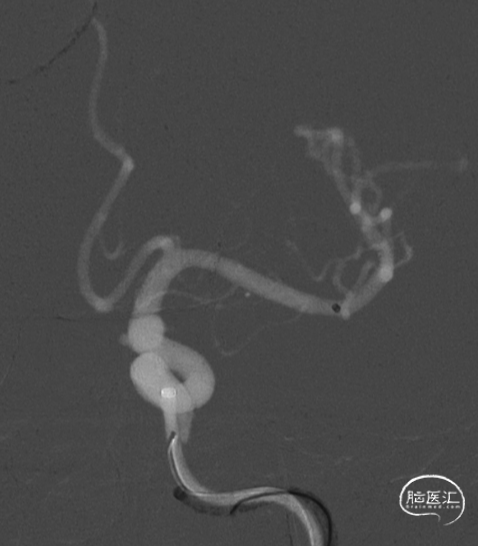

经桡动脉入路左侧颈内动脉通路建立

选择工作角度

压颈试验:前交通开放

Fastrack微导管到位

TB Plus 4/35